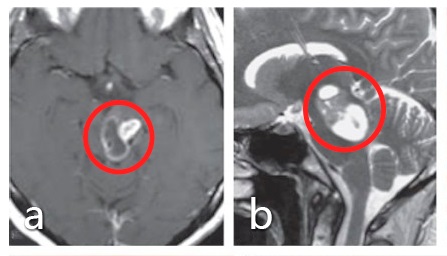

术前:a、b图术前MRI显示脑干中脑占位,肿瘤导致导水管闭塞。

手术入路和体位:c图表示半坐位进行了手术,通过左侧小脑上天幕下入路全切肿瘤。d图显示整个外侧枕骨区域暴露在下,直到滑车神经出口(箭头所示)。e图表示脑干的进入点选择在上丘脑的侧面,然后的肿瘤切除腔约6mm

术后:f、g图术后MRI影像显示肿瘤得到了全切。患者无并发症,无其他神经系统缺陷。术后病情平稳,术后5年内无肿瘤复发。